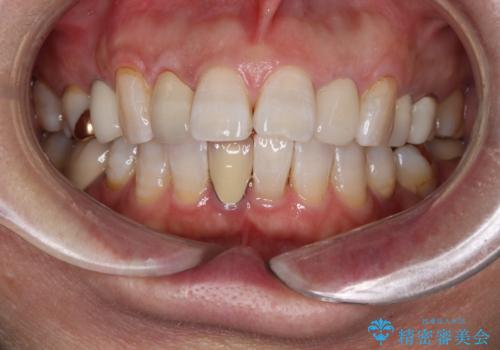

セラミッククラウン作成の為のオフィスホワイトニング

- セラミックの治療にあたりご自身の歯の色を明るくしたいとの希望でオフィスホワイトニングの施術をしました。

ご自身の歯が白く変わったので、その後のセラミック治療にも明るく白いセラミックにできると喜んでいただけました。